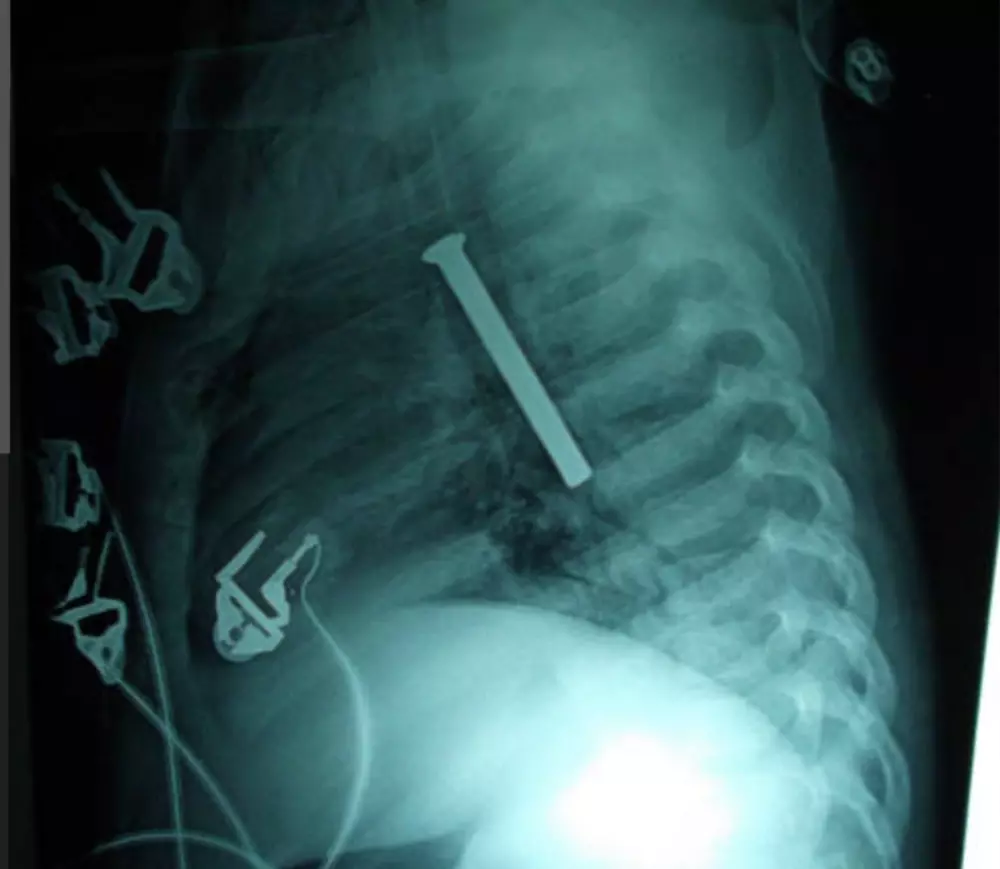

اقدم لك دوره تدريبيه من خلالها يمكنك قراءة أشهر 25 تحليل وتقارير جميع انواع الأشعه مع التطبيق عمليا من خلال إحضار تقارير ونتدارسها سويا وذلك لاطمئنانك فقط قبل الذهاب للطبيب المختص أو للعلم إن كنت من طلاب المجال الطبي الدوره متاحه للجميع لا يشترط أن تكون من طلاب المجال الطبي فقط فهي للعلم والمعرفه وليست للتشخيص والعلاج من خلال هذه الدور سوف تتعلم 1.أسماء التحاليل ومتى تطلب من المريض 2.النسب الطبيعيه للعناصر والمواد الكيميائيه الموجوده في الجسم 3.سبب ارتفاع أو انخفاض هذه النسب وما المترتب على ذلك 4.ستعرف أيضا مما يعاني صاحب التحليل أو الأشعه 5. أعلمك كيف تقرأ تقرير الأشعه باستفاضة ومعرفة نتيجته 6.اعلمك الفرق بين انواع الاشعه مثل الأشعه المقطعيه والرئتين المغناطيس والأشعه بالصبغة والأشعه التداخليه والأشعه السينية والمسح الذري ومتى تطلب كل واحده 7.اعلمك قراءة الفيلم الموجود مع التقرير وكيف تظهر الدهون في الاشعه والعظام المكسوره وكيف تظهر الدهون وجميع أنسجة الجسم في الفيلم (الفيلم هو الورقه السوداء) الموجوده مع التقرير 8.كيف تظهر الأورام والجلطات في الأشعه مدة الدوره 3 ايام بمقدار ساعتين يوميا عبر موقع زوم أو تيشمنت بالإضافه إلى شهادة حضور موثقه في نهاية الدوره أول يومين للتدريب والتعرف على تقارير التحاليل اليوم الثالث للأشعه سعر الدوره كامله شامله ال3 ايام وشهادة الحضور 30 دولار فقط إن لم تستفيد من الدوره يمكنك استرداد المبلغ واطمأن لن تسترده لأنك حتما ستستفيد 100% والسلام